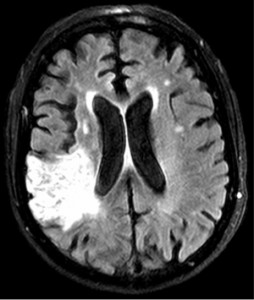

A process developed to increase efficiency and

productivity in Japanese car factories has helped improve stroke

treatment at Barnes-Jewish Hospital, report researchers at Washington

University School of Medicine in St. Louis.